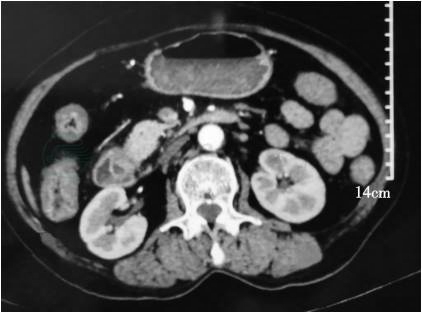

2020-03-15:当地医院腹部增强CT(图1~图3)示壶腹占位,大小约1.2cm×1.8cm,动脉期可见强化,肝内外胆管,胆总管及胰管扩张,胆总管最大内径约1.3cm,胰管最大径约0.5cm。当地医院血生化检查:白蛋白22g/L,总胆红素146μmol,直接胆红素102μmol。

图1 壶腹部占位

图2 胆总管扩张

图3 胰管扩张